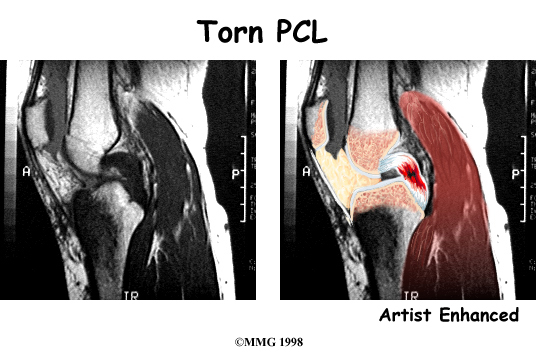

The magnetic resonance imaging (MRI) scan is probably the most accurate test without actually looking into the knee. The MRI machine uses magnetic waves rather than X-rays to show the soft tissues of the body. This machine creates pictures that look like slices of the knee. The pictures show the anatomy, and any injuries, very clearly. This test does not require any needles or special dye and is painless.

Ruptured PCL

More recent research has shown us that the PCL also prevents medial-lateral (side-to-side) and rotatory movements. This confirms the suspicion that the PCL’s effect on knee joint function is more complex than previously thought.